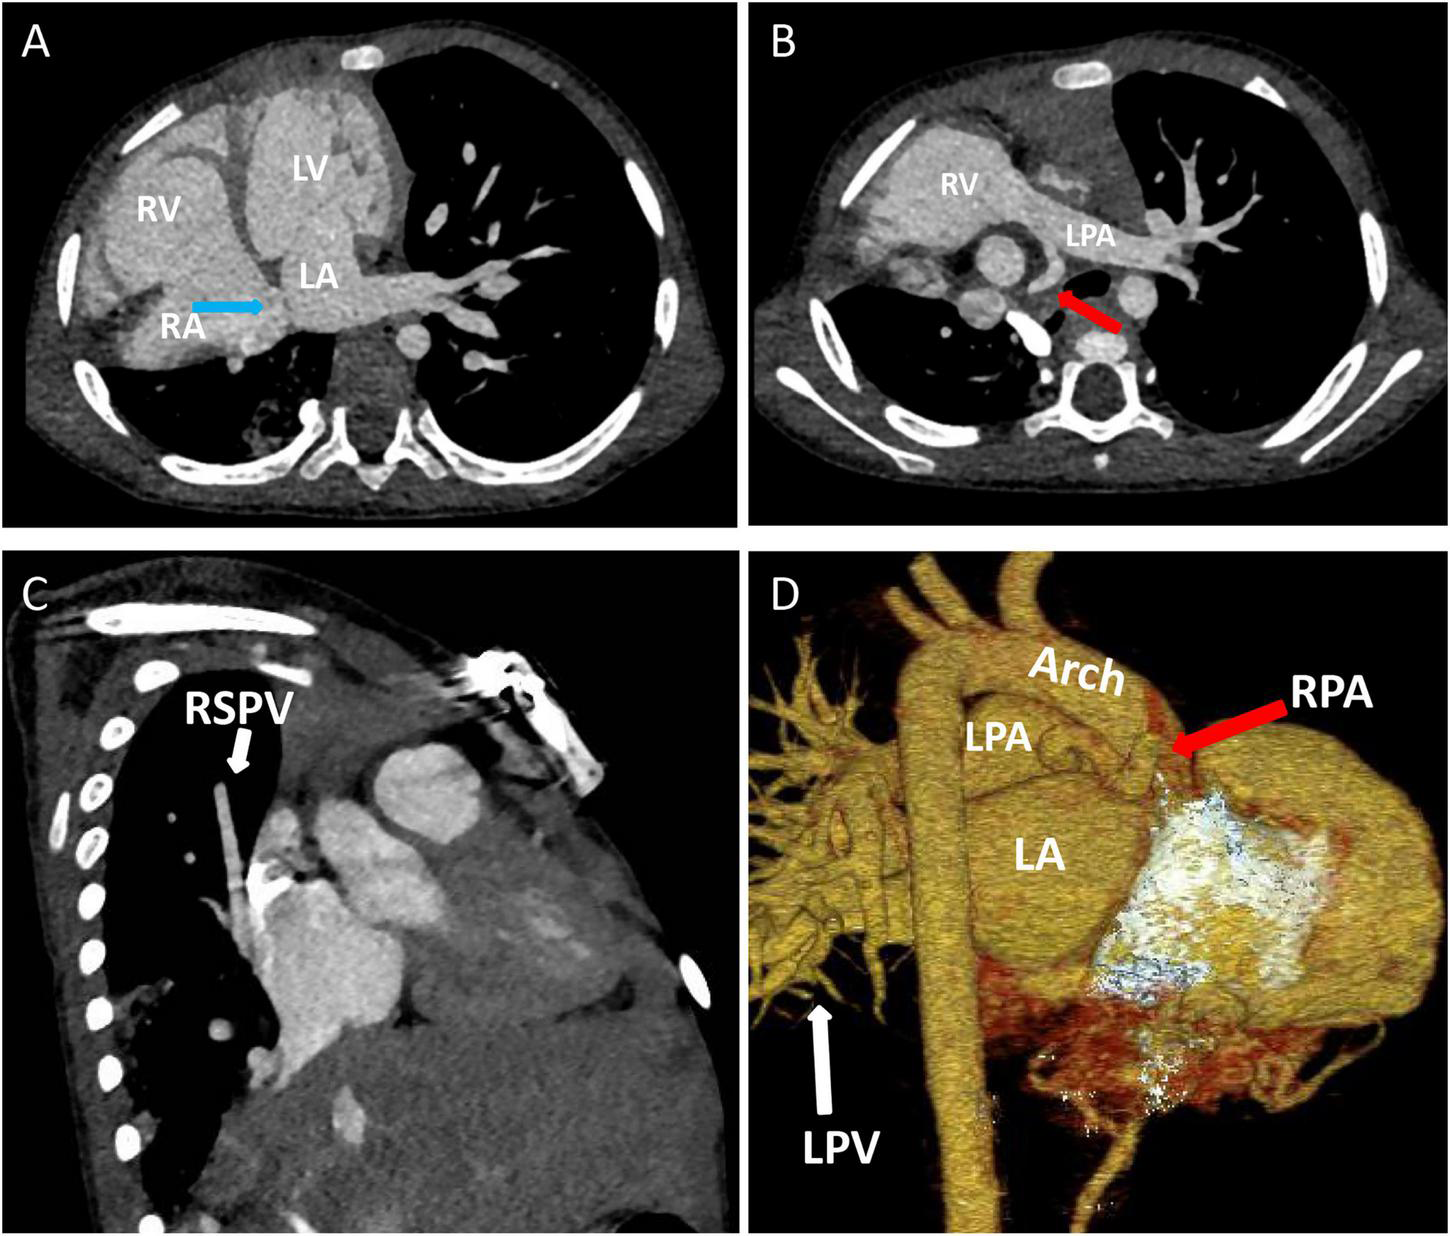

Chest X-ray showed a large area of high density in the lower right lung. Chest CT showed a 9 mm defect in the atrial septum (Figure 1A), a significantly small right pulmonary artery (∼5 mm) and a significantly small right superior pulmonary vein (Figures 1B–D), a small and sparsely branched right lung, and the venous of sequestration lung return to the hepatic vein (Figure 2). Considering the patient’s young age and inability to tolerate cardiac and pulmonary surgery, isolated pulmonary embolism and atrial septal occlusion were performed under general anesthesia. Digital subtraction angiography (DSA) and CT 3D reconstruction (Supplementary Video) showed an abnormal blood vessel branching from the right renal artery opening (∼4 mm; Figures 3A–C), and arching toward the right lower lung for blood supply. During the operation, nine coils of equal size were applied to completely block the abnormal blood supply to the right lower lung. Under transthoracic ultrasound guidance, a 14 mm atrial septal occluder was placed through the delivery sheath and ascertained to be adequately fixed, with no residual shunt and intact valvular apparatus (Figure 3D).

FIGURE 1

Contrast-enhanced CT of the chest and three-dimensional cardiac computed tomography angiography: (A) Atrial septal defect location, ∼9 mm in size (blue arrow). (B–D) The right pulmonary artery (red arrow) and right superior pulmonary vein are hypoplastic (white arrow). LA, left atrium; LPA, left pulmonary artery; LPV, left pulmonary vein; LV, left ventricle; RA, right atrium; RPA, right pulmonary artery; RSPV, right superior pulmonary vein; RV, right ventricle.